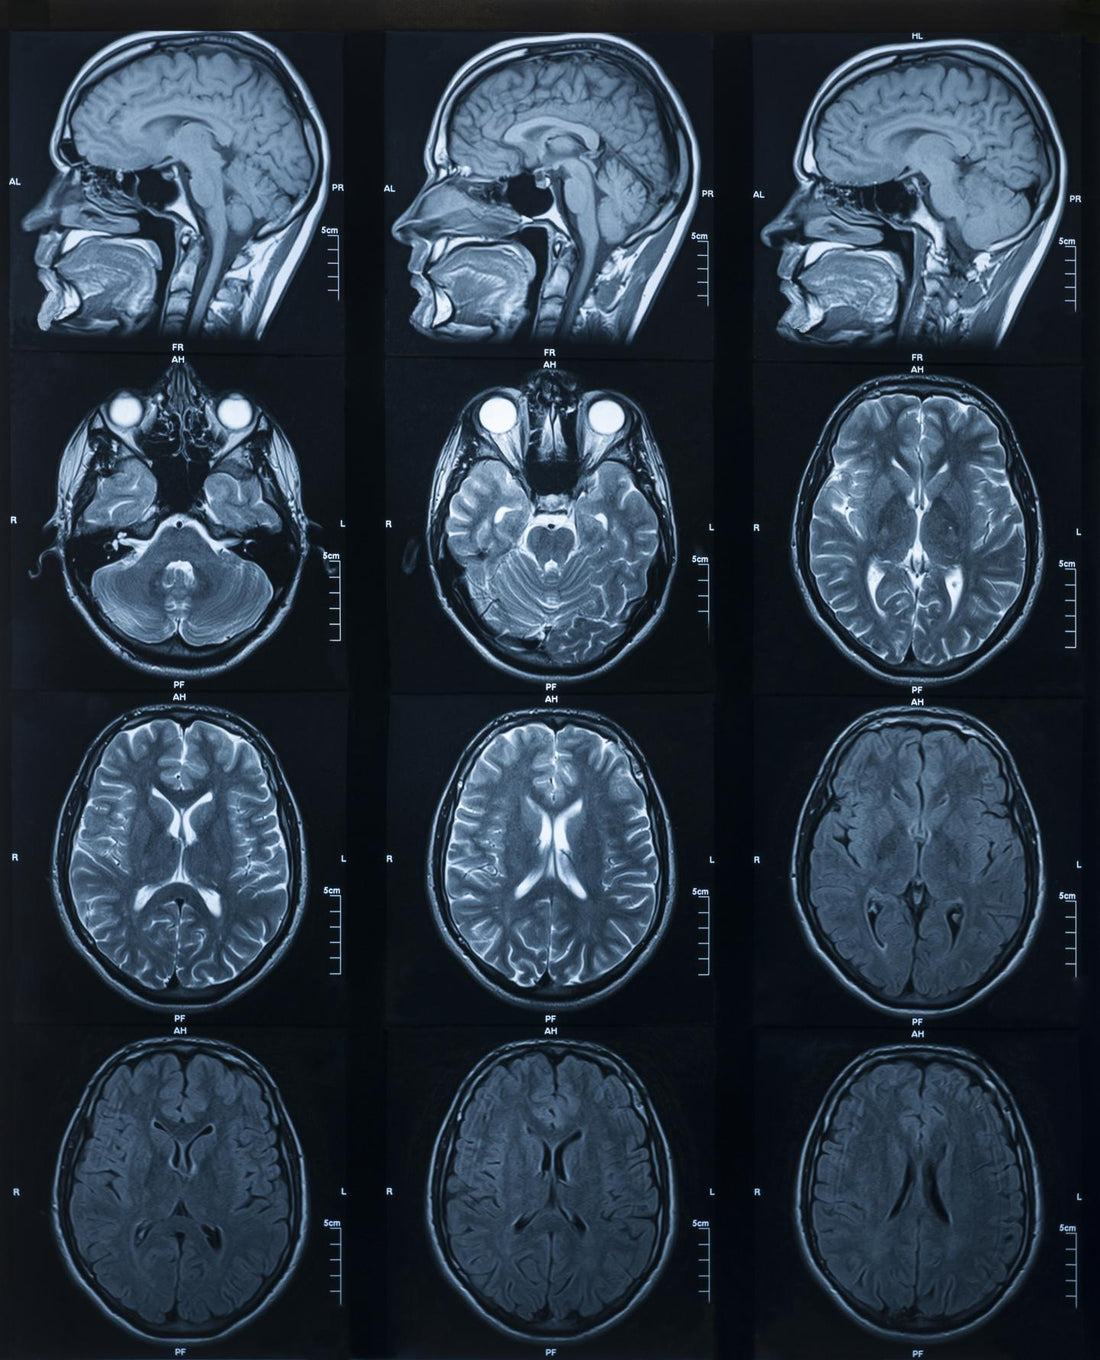

Mechanistic Benefits of Lithium in the Brain

Lithium’s clinical applications are well documented. What’s discussed less often are the underlying biological mechanisms that drive its effects. To understand why lithium works, we need to look beyond symptoms... Read more...